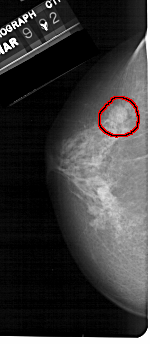

ics_version 1.0 filename A-1317-1 DATE_OF_STUDY 9 3 1992 PATIENT_AGE 68 FILM FILM_TYPE REGULAR DENSITY 4 DATE_DIGITIZED 28 7 1998 DIGITIZER HOWTEK 43.5 SEQUENCE LEFT_CC LINES 5146 PIXELS_PER_LINE 2236 BITS_PER_PIXEL 12 RESOLUTION 43.5 OVERLAY LEFT_MLO LINES 5491 PIXELS_PER_LINE 2611 BITS_PER_PIXEL 12 RESOLUTION 43.5 OVERLAY RIGHT_CC LINES 5281 PIXELS_PER_LINE 2341 BITS_PER_PIXEL 12 RESOLUTION 43.5 NON_OVERLAY RIGHT_MLO LINES 5491 PIXELS_PER_LINE 2911 BITS_PER_PIXEL 12 RESOLUTION 43.5 NON_OVERLAY |

FILE: A_1317_1.LEFT_MLO.OVERLAY TOTAL_ABNORMALITIES 1 ABNORMALITY 1 LESION_TYPE MASS SHAPE ROUND MARGINS CIRCUMSCRIBED ASSESSMENT 4 SUBTLETY 3 PATHOLOGY BENIGN TOTAL_OUTLINES 1 BOUNDARY |

FILE: A_1317_1.LEFT_CC.OVERLAY TOTAL_ABNORMALITIES 1 ABNORMALITY 1 LESION_TYPE MASS SHAPE ROUND MARGINS CIRCUMSCRIBED ASSESSMENT 4 SUBTLETY 3 PATHOLOGY BENIGN TOTAL_OUTLINES 1 BOUNDARY |